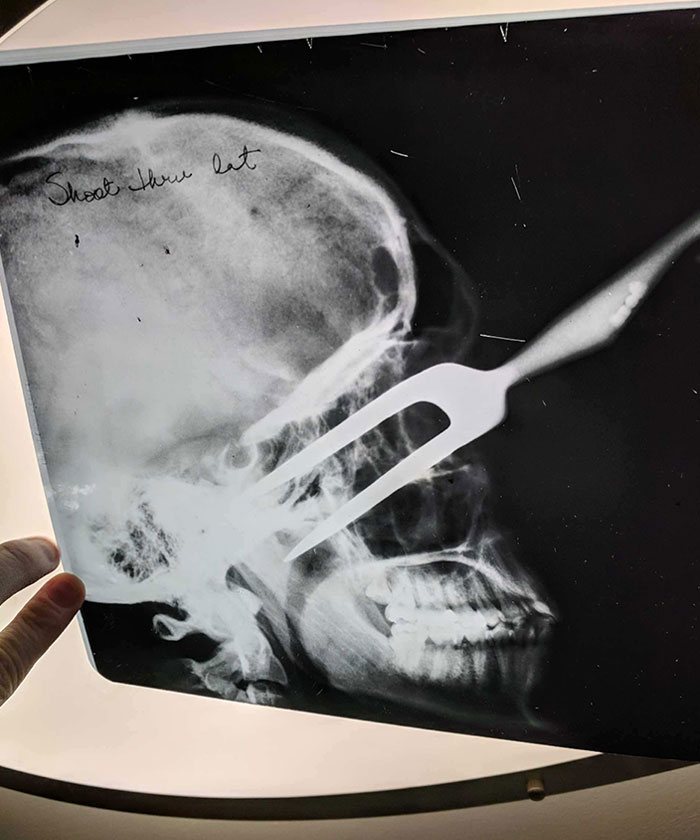

2. Môj kamarát si nedávno kúpil dom. V starej krabici našiel tieto röntgenové snímky.